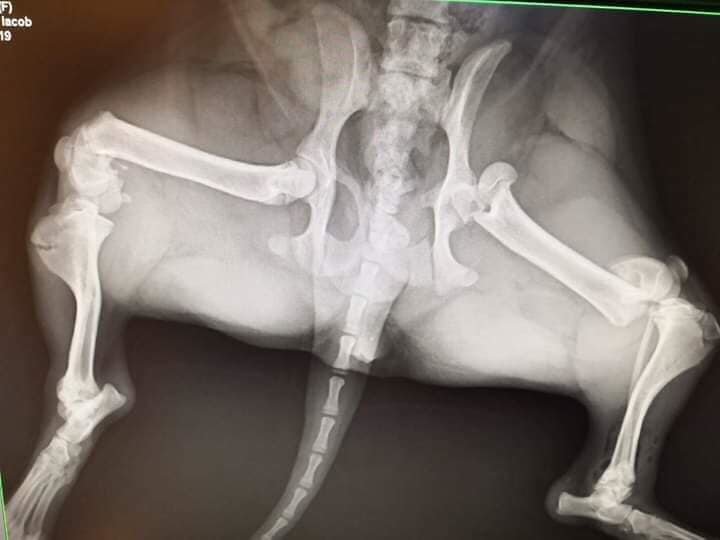

Meet Cleo. She was found in a ditch on the side of the road having been hit by a car. She had 3 broken bones in 2 legs. Her rescuer, Ani, could not afford to pay a vet for the massive veterinary costs that were being quoted by local vets, so Ani asked for our help. We welcomed Cleo into our Homeless Animals Hospital program.

Cleo needed her severly damaged leg to be amputated. She is learning to walk on three legs now. She is recovering at Family Vet in Craiova, and remarkably our Suzy has found her a great home in the UK!